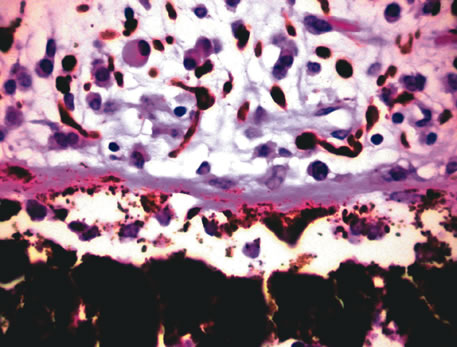

Inflammatory conditions may also lead to iris nodules. Patients suffering from fungal endophthalmitis may demonstrate an irregular yellow-white mass on the iris. Histologically, these appear as necrotizing granulomas containing mycotic agents (Fig. 2). In juvenile xanthogranuloma, a yellowish-gray iris lesion may be associated with spontaneous hyphema, and histopathologically the nodules demonstrate diffuse histiocytic infiltrate (Fig. 3). Multinucleated giant cells displaying peripheral foamy cytoplasm are also noted; these cells are known as Touton giant cells.29 The giant cells and the histiocytes contain lipid that can be demonstrated by oil red O stain.

Fig. 2. Coccidioidomycosis. Iris stroma shows necrotizing granuloma containing mycotic organisms. The organisms show features of Coccidioides immitis. (Hemotoxylin-eosin ×60.)